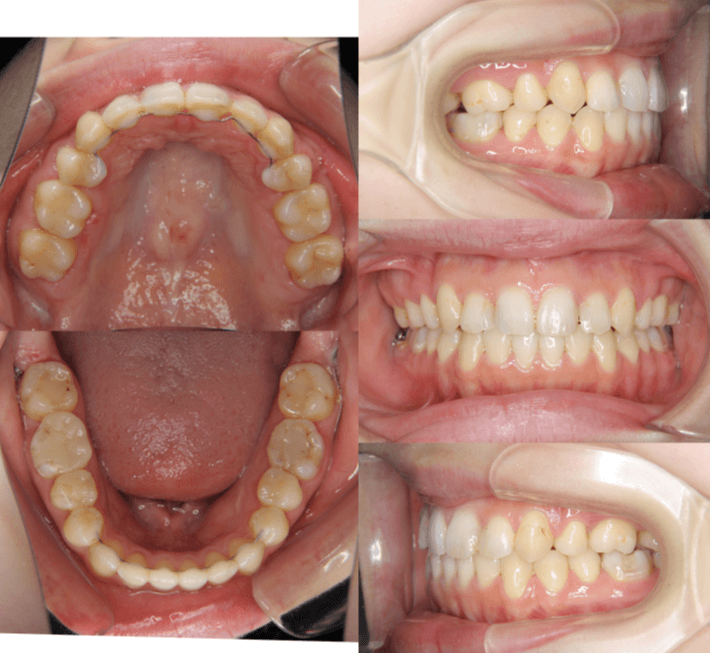

| 年齢・性別 | 22歳女性 |

|---|---|

| 主訴 | 上下顎前歯部に開咬と口元の突出感を気にされて来院された22歳女性。咬み合わせや審美的な改善を希望されていました。 |

| 治療期間・回数 | 3年9ヶ月・32回 |

| 費用 | 930,000円 |